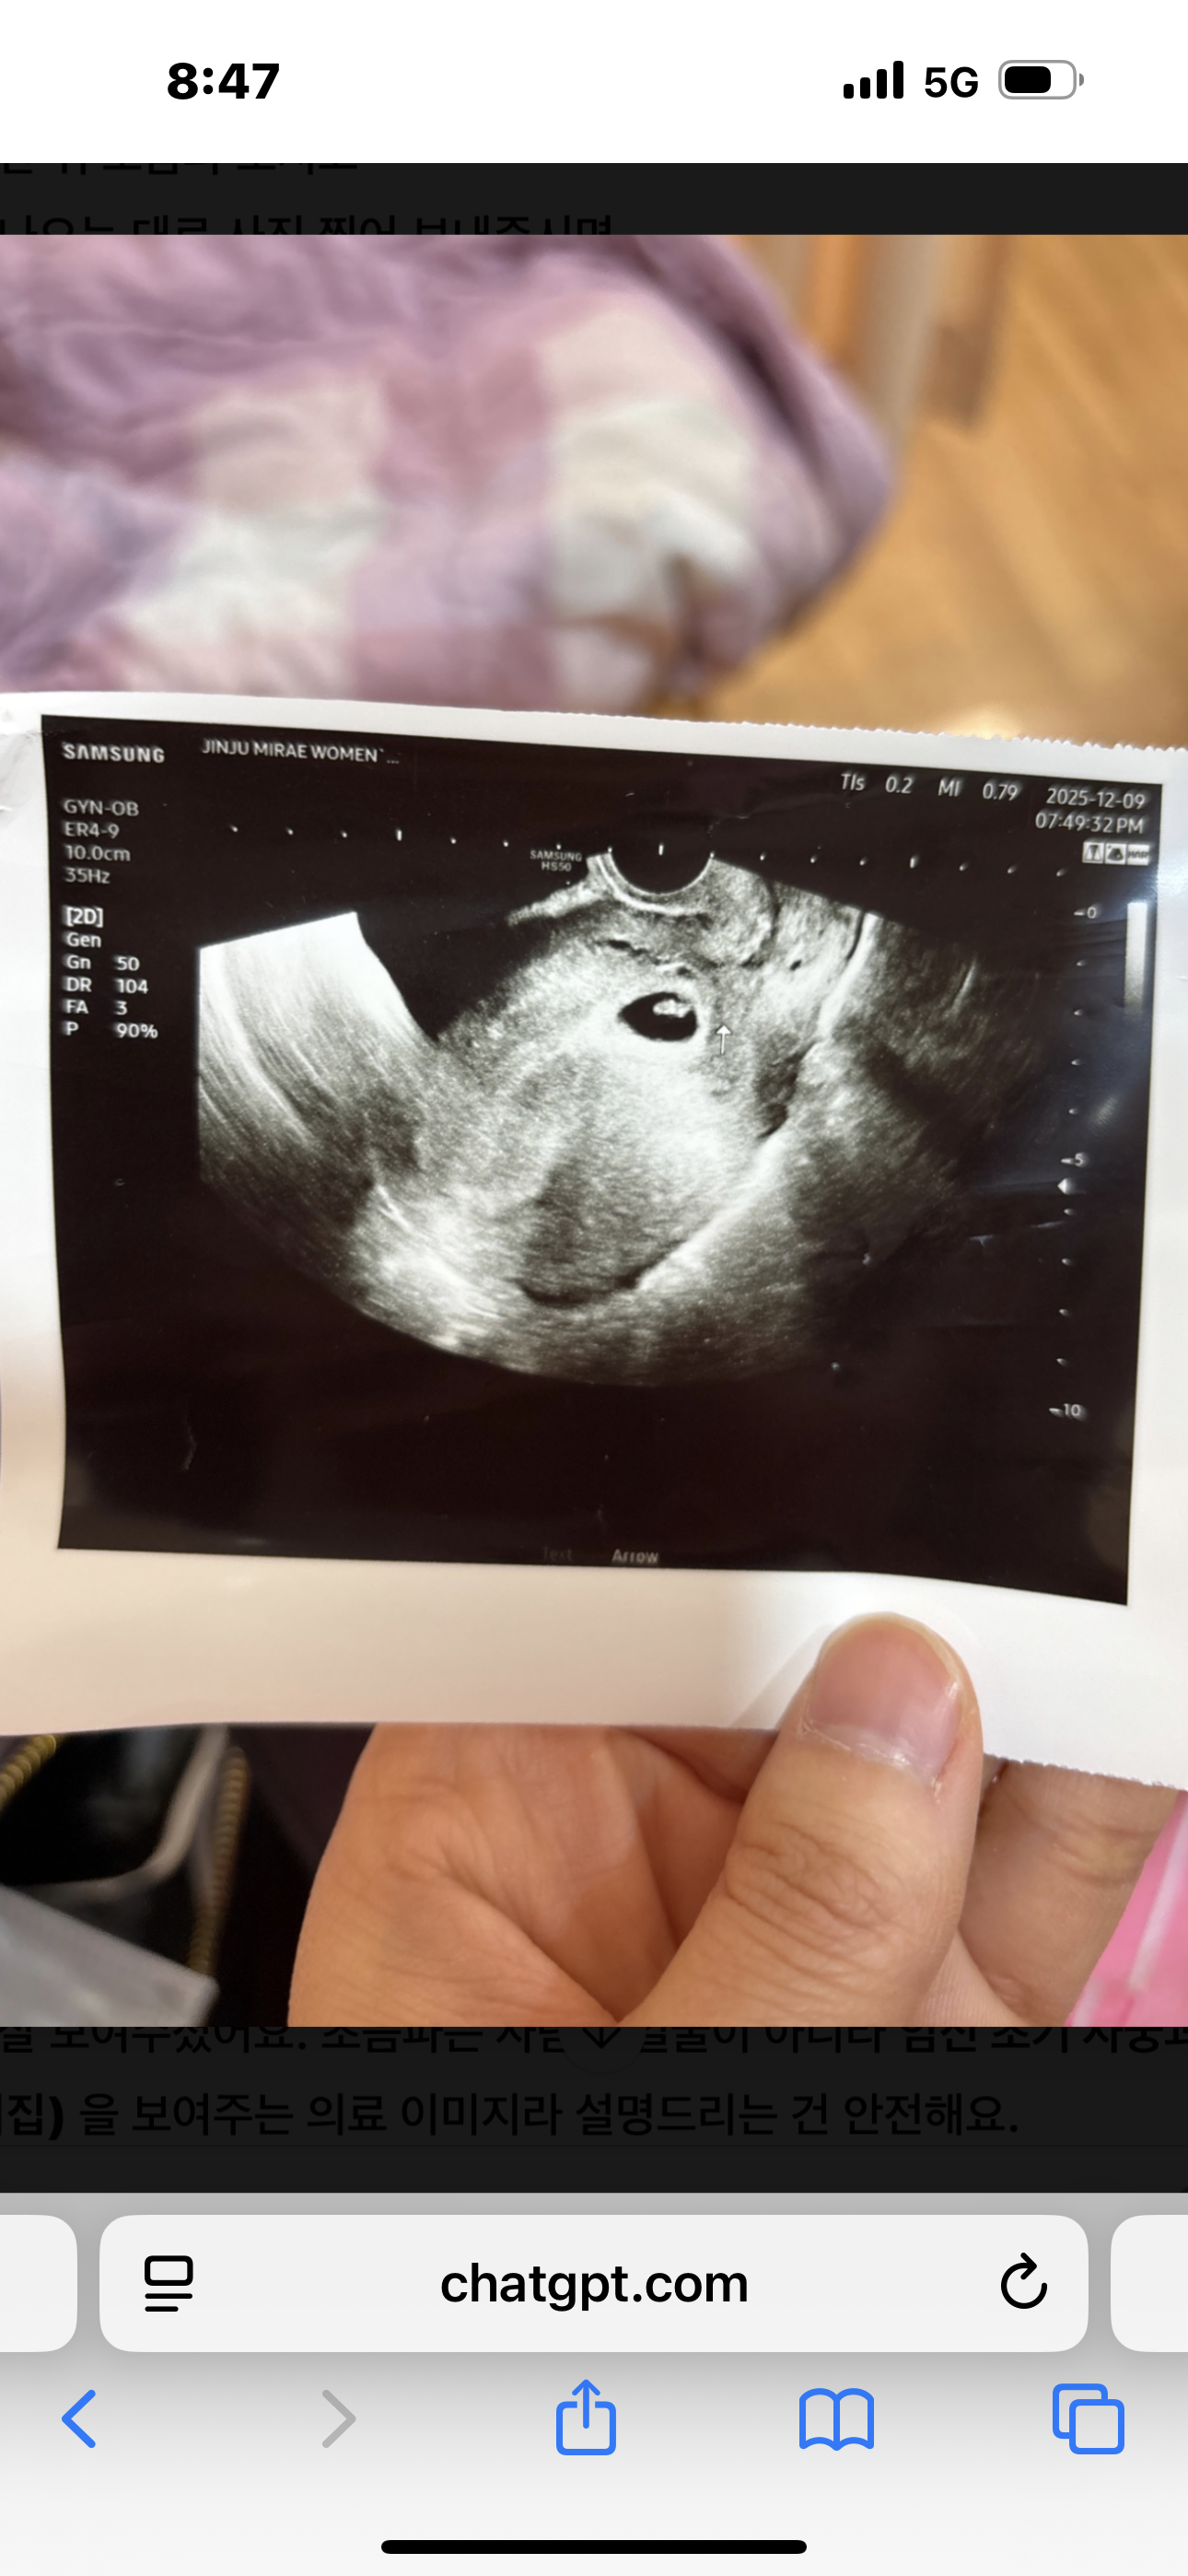

아기집이 아래 잇어서 입원했어요

임신 7주2일차에요 아기집이 아래에잇고 용종이잇어서 제거 하고 입원 했어요 너무 걱정되고 불안해요 오늘 선홍빛 피가 보여서 급하게 산부인과 왓더니 입원해라고 누워잇어야 한다해서 2일 입원 치료 권고받앗네요 ㅠㅠ